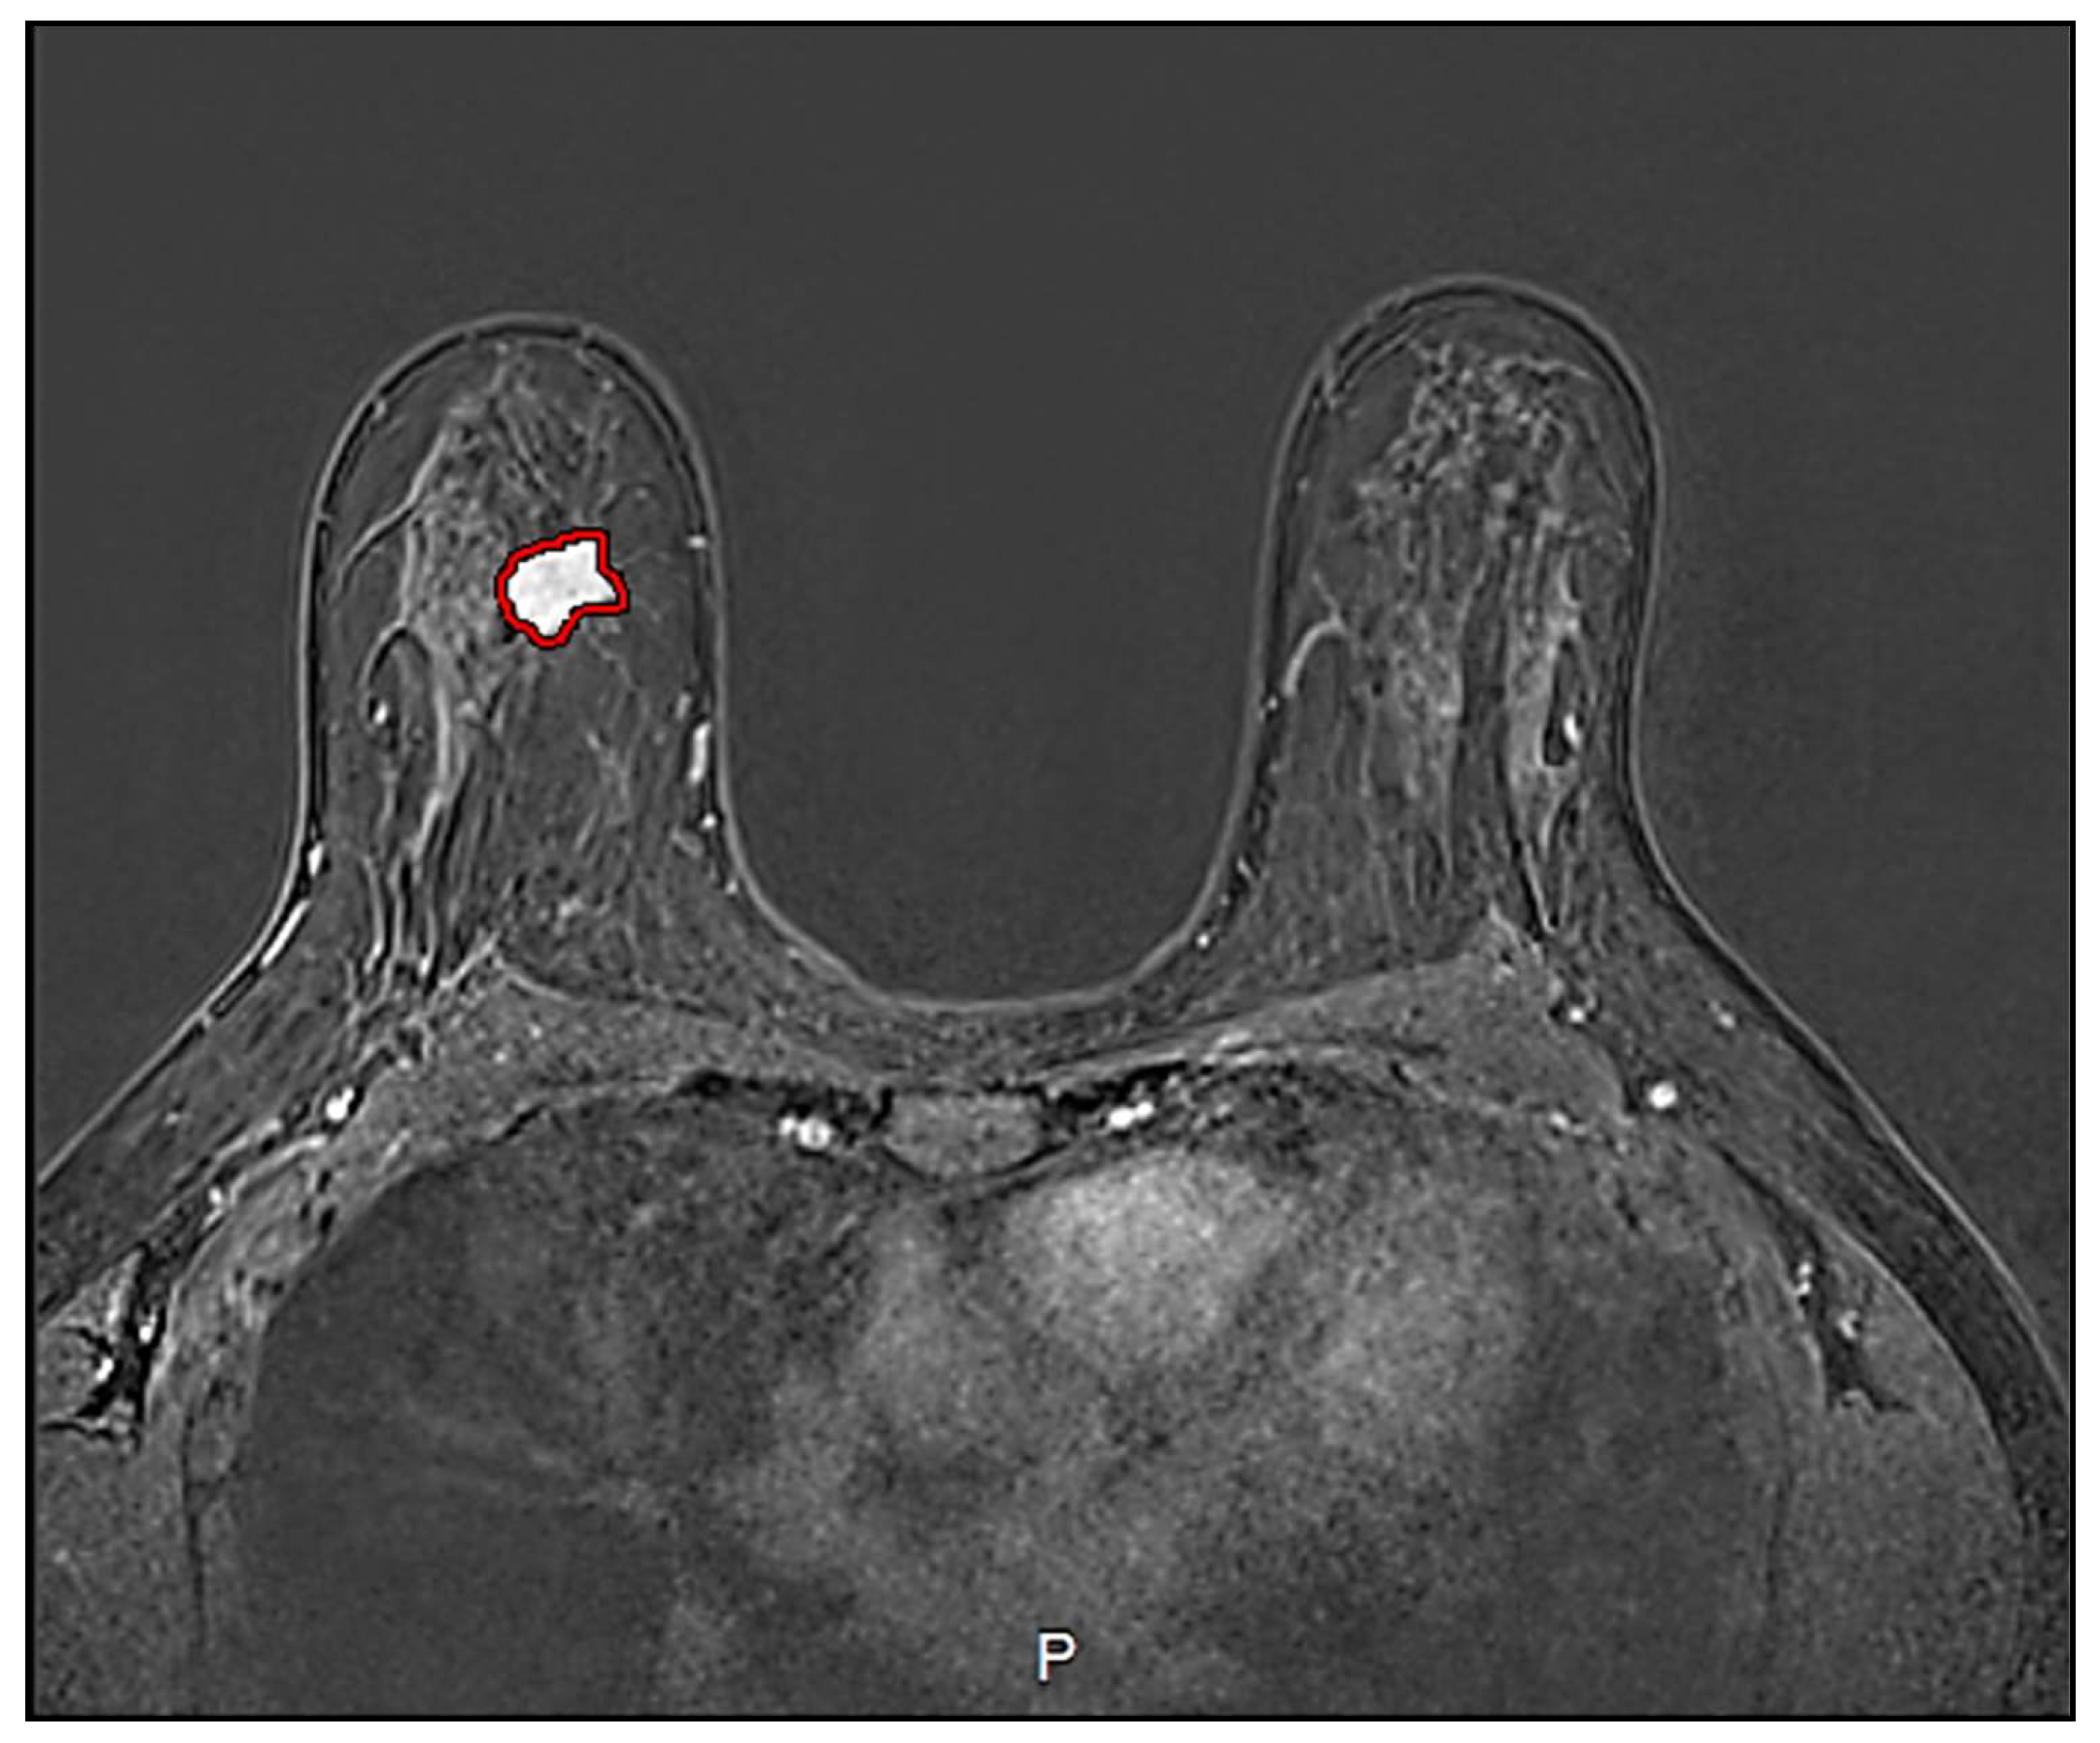

2.4. Image Processing